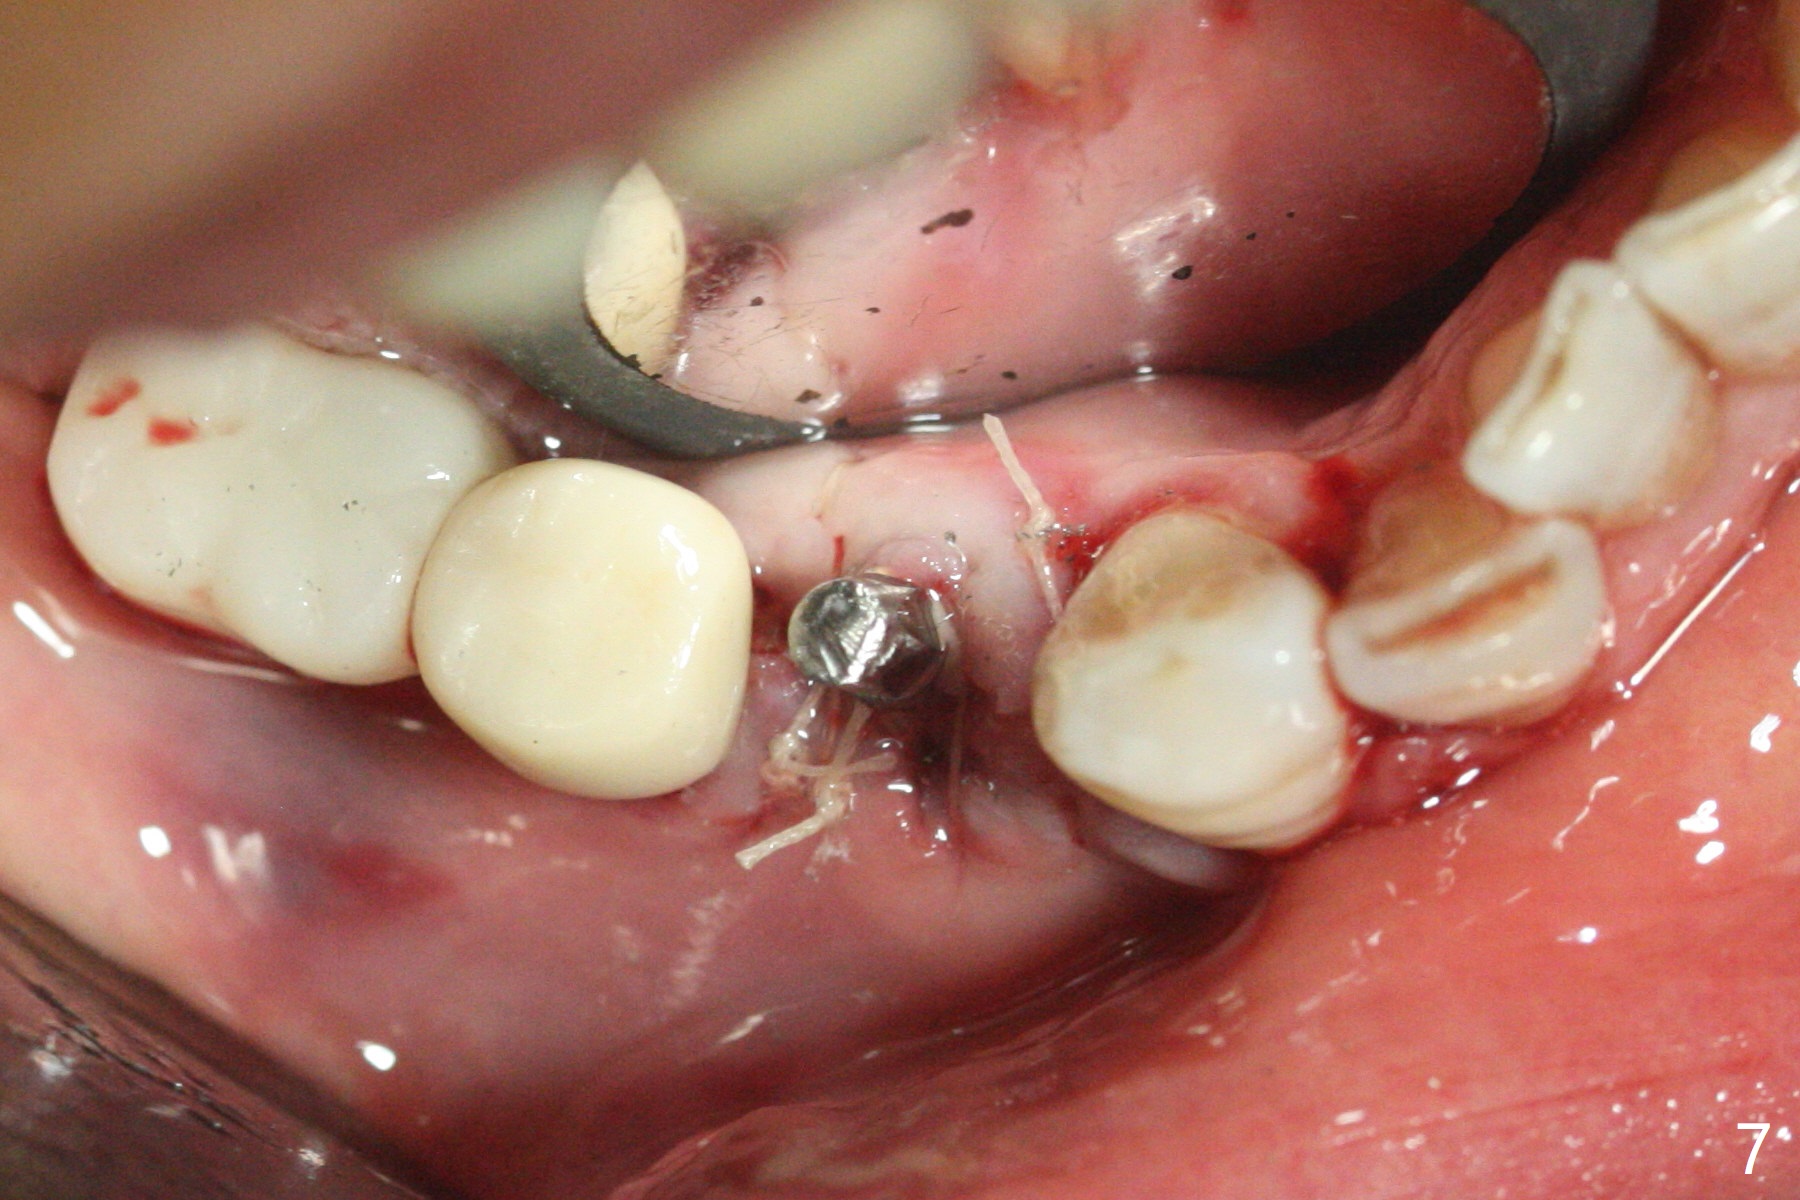

61岁女右下4(粘固后5.5年)植体周围炎(颊侧牙龈没有角化龈(图一:*)),因为颊侧种植(图二),翻瓣证实(图三),取出4.5毫米两段式植体,在舌侧骨质(图四:L)即刻植入2.5毫米一段式植体(图五),颊侧缺损植入大量粘性骨粉(图六:*),覆盖PRF膜后,缝合(图七),与图二对比,窄植体明显舌侧移位。术后一个月撤除牙周敷料(图八),并没有马上制作临时牙冠,让病人容易搞好局部卫生,促进伤口愈合(图九),术后三个月塞入龈线(图十:^),制备基台,植体在牙槽嵴中性位置(颊舌侧),但愿颊侧有足够再生骨质,覆盖植体螺纹。